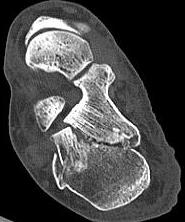

• 关节镜技术联合钉中钉系统全内修复跟骨关节内骨折的临床疗效观察

2026, 32(1):19-25. DOI: 10.12235/E20250392

摘要 (74) HTML (35) PDF 2.90 M (82) 评论 (0) 收藏

摘要:目的 探讨关节镜技术联合钉中钉系统全内修复跟骨关节内骨折的临床疗效。方法 回顾性分析2021年5月-2024年4月该院骨与关节康复科收治,并获得随访的31例闭合性跟骨关节内骨折患者的临床资料。均采取关节镜技术联合钉中钉系统全内修复手术治疗方案。术前及术后均行跟骨侧轴位X线片及足部CT检查,根据影像学结果对骨折类型进行分型,并评价术后骨折复位情况。比较手术前后跟骨高度、宽度、Bohler角和Gissane角。记录术前等待时间、手术时间、术中出血量、住院时间、术后疼痛视觉模拟评分法(VAS)评分等围手术期相关指标及术后并发症发生情况。采用美国足踝外科协会(AOFAS)评分和Maryland足部评分评估临床疗效。结果 术后影像学检查,可见跟骨术后关节面塌陷骨块复位;跟骨高度明显高于术前,跟骨宽度明显窄于术前,Bohler角较术前明显增大,Gissane角较术前明显缩小,差异均有统计学意义(P < 0.05)。术前等待时间为6(4,7)d,手术时间为(188.77±39.53)min,术中出血量为(59.03±23.00)mL,住院时间为(16.49±4.04)d,术后疼痛VAS评分为2(1,2)分,AOFAS评分为92(90,95)分,Maryland评分为92(90,95)分。结论 采用关节镜技术联合钉中钉系统全内修复跟骨骨折,具有可早期开展手术、创伤小、直视下复位、固定可靠和无切口相关并发症等优点,适用于Sanders Ⅱ型和Ⅲ型跟骨骨折。值得应用于临床。